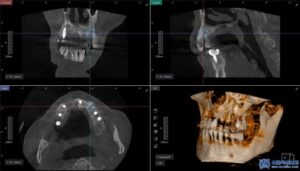

이는 컴퓨터 분석을 통해 미리 계산된 경로를

기반으로 임플란트를 식립하는 방식으로,

수술가이드를 활용하여 절개 없이도

정밀한 수술이 가능한데요.

임플란트 성공률에서 중요한 요소 중

하나는 식립각도로,

식립각도가 임플란트 성패에 얼마나 영향을

주는 지에 관한 연구도 뉴스로 발표되었습니다.

서울박사치과에서는 컴퓨터 시뮬레이션을 통해

최적의 식립 위치와 각도를 미리 계산하여

수술을 진행합니다.